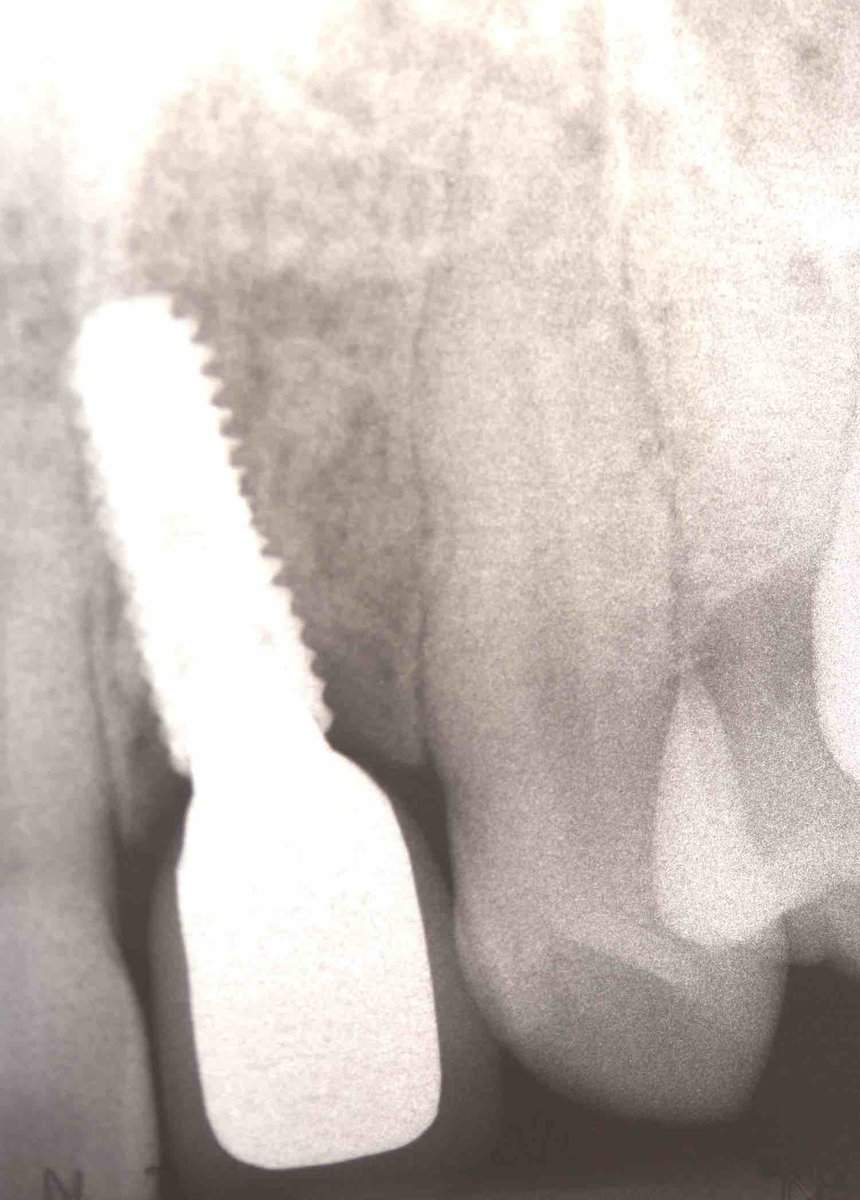

Established Mucositis and swelling buccal of the 22, initially attributed to absence of keratinised mucosa and thus referred for soft tissue augmentation. Studying the CBCT however, in combination with the clinical examination, one can see the main problem here to be the implant position. In particular the bucco-palatal angle results in the implant shoulder  being too buccal. As a result the cement retained prosthesis is also protruding in its apical part, resulting to recession beyond the mucogingival line. Unless we can correct the implant position and the crown, any intervention targeting the soft tissues alone is likely to make the problem even worse.